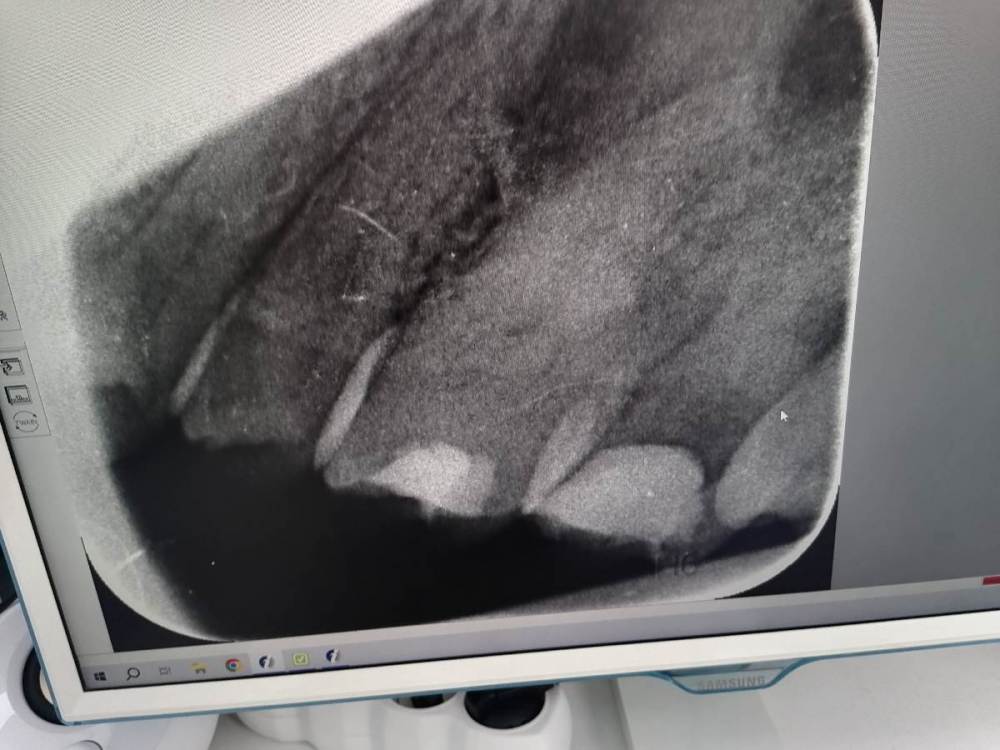

Добрый вечер. Здравствуйте. История такая две недели заходился зуб от любой еды и питья. Пошла в поликлинику с острой болью. Там мне вскрыли пломбу, сказали будут удалять нерв. Положили хрен знает что под временную пломбу. Сказали приходить минимум через неделю. Скажите пожалуйста, первый раз с таким сталкнулась(от шока и боли ничего не помню). Возможно ли вылечить нерв? И кто разбирается в снимках, на нем видно, что с нервом что то не то зуб крайний правый

здравствуйте, качество снимка не позволяет его интерпретировать. С Ваших слов предположу, что кариес осложненный, и доктор лечит его в 2 посещения с использованием препарата для дэвитализации пульпы ( "умерщвления нерва")